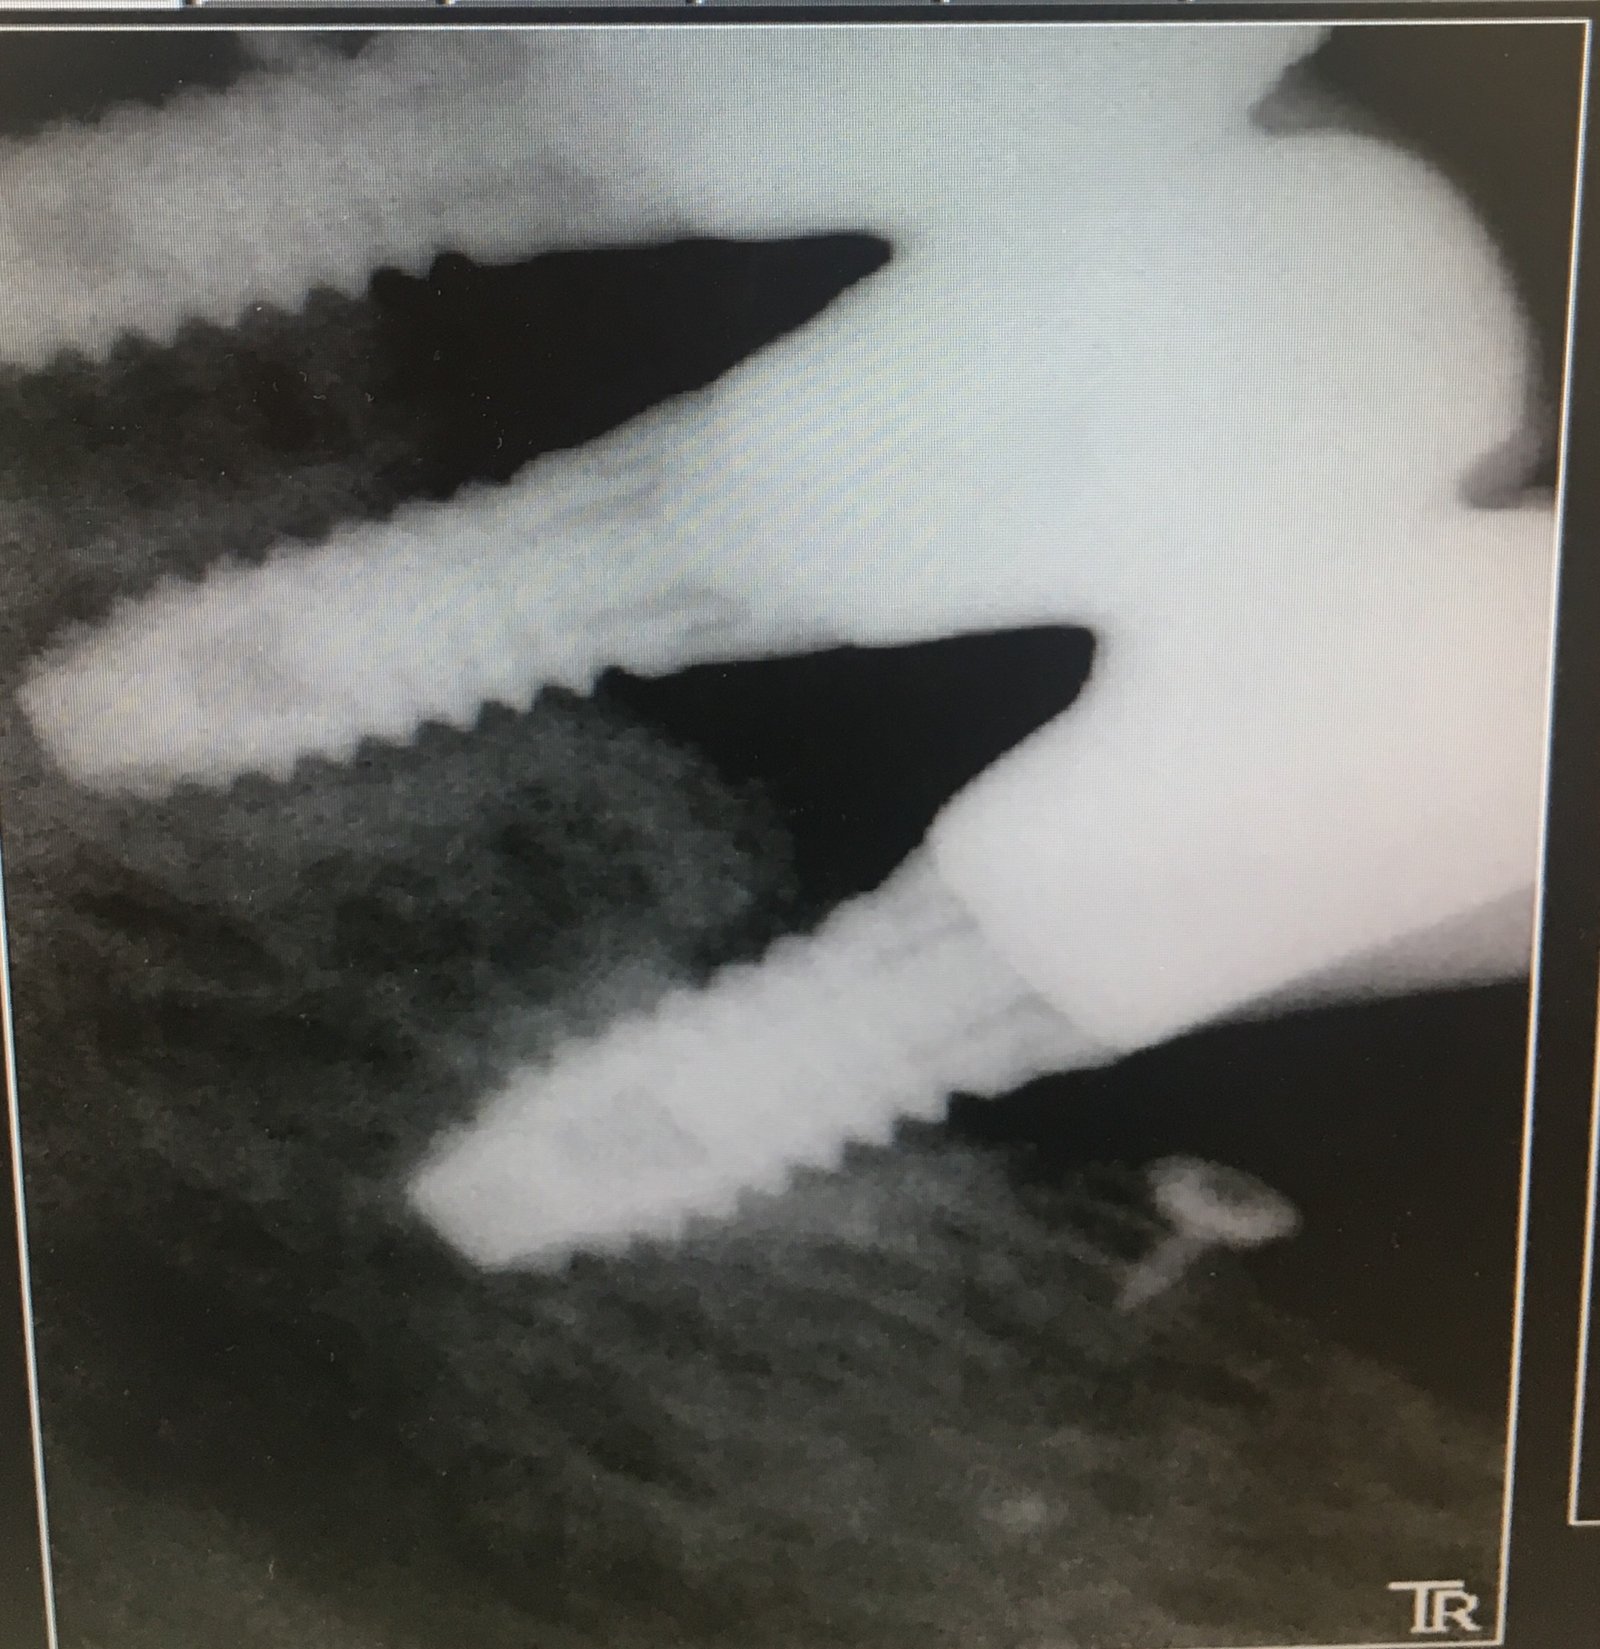

Buenas tardes compañeros! Necesito ayuda para saber que implante lleva este paciente. Lo único que se es que se lo pusieron como para 2013 en una franquicia de Adeslas de [...]